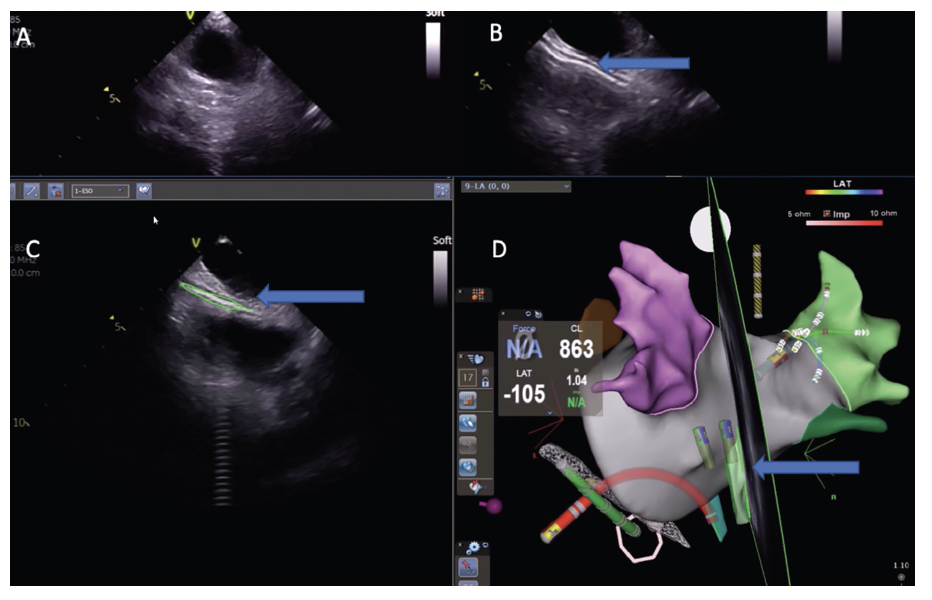

Anesthesiologists intubate with a short-acting paralytic, typically succinylcholine, which wears off quickly, allowing pacemapping of the right phrenic nerve on the anterior side of the right pulmonary veins (PVs). After phrenic nerve mapping, the patient is paralyzed with a larger dose of rocuronium to avoid map shifts during the case. During ablation, improved catheter stability is achieved by using a high frequency, low tidal volume ventilatory protocol with the ventilator set at 30 breaths/minute at a tidal volume of 200 cc. The improved map and catheter stability achieved through paralysis and high-frequency ventilation have reduced our ablation time by 23% compared with nominal ventilator settings. Prior to ablation, the location of the esophagus is identified using both radiopaque contrast (gastrografin) as well as echo contrast (Definity, Lantheus). This allows for both edges of the esophagus to be seen and mapped onto the left atrial map using CartoSound (Biosense Webster, Inc) (Figure 2). While paralyzed, we are then able to deviate the esophagus using the EsoSure Esophageal Retractor (EsoSure) and remap the esophagus in the new location. The location of the esophagus can also be confirmed using a few seconds of fluoroscopy after deviation (Figure 3). Because we can be confident the esophagus is not adjacent to our lesion path, power is set at 50W for ablation around the PVs and Visitag (Biosense Webster, Inc) settings are set for an impedance drop of 10 Ohms, which we will target up to an Ablation Index of up to 500 on the posterior wall and 550 on the anterior wall. At the end of the case, the paralytic is reversed with sugammadex. This allows the patient to quickly wake up, reducing the time to extubation.